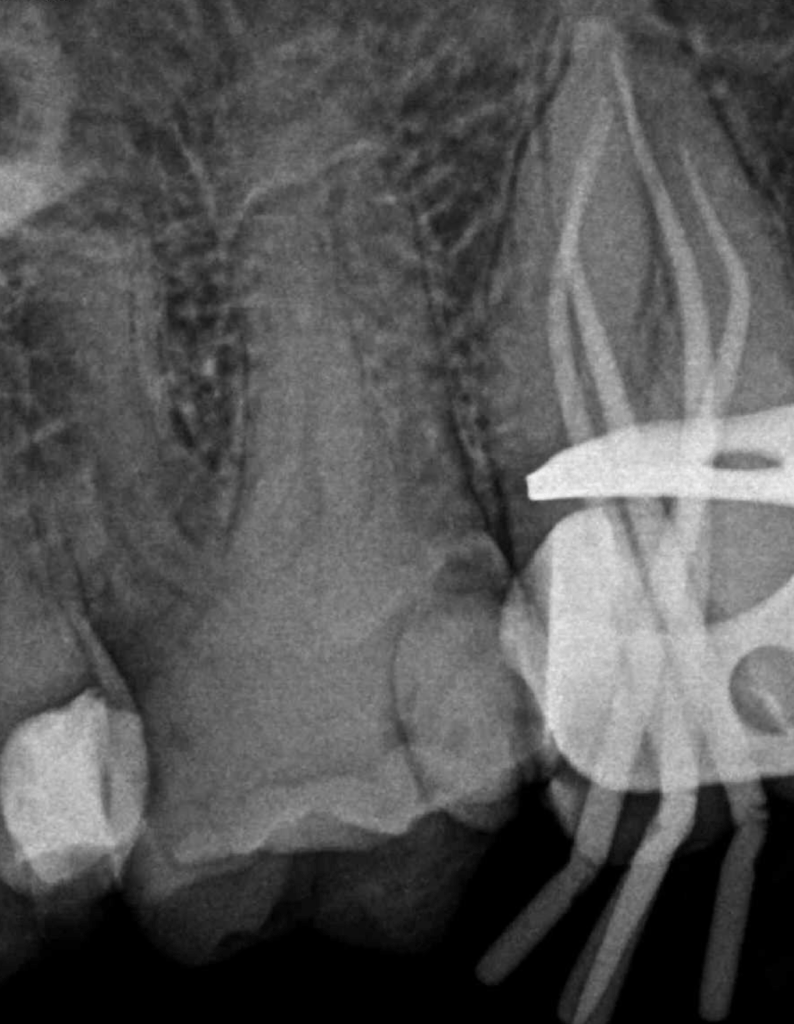

Reco preendo + 4 conductos molar superior